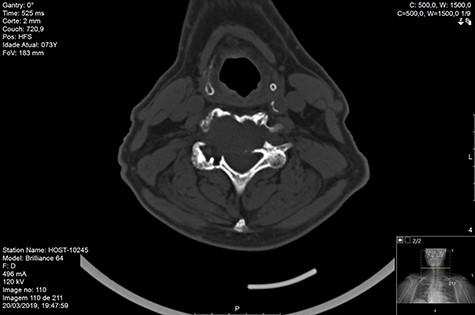

Computed tomography (CT) (Figs 1–3) and magnetic resonance imaging (MRI) (Figs 4–6) of the cervical spine were performed and revealed a lytic lesion involving most of C4, C5 and C6 vertebral bodies with bilateral extension to the posterior spinal elements of C4 and C5 and complete disruption of C4-C5 and C5-C6 intervertebral discs.

The Spinal Instability Neoplastic Score (SINS) [4, 6, 7] for assessing spinal instability from metastatic disease was used and the lesion was deemed unstable (SINS 13), with impending risk of increased neurological damage.